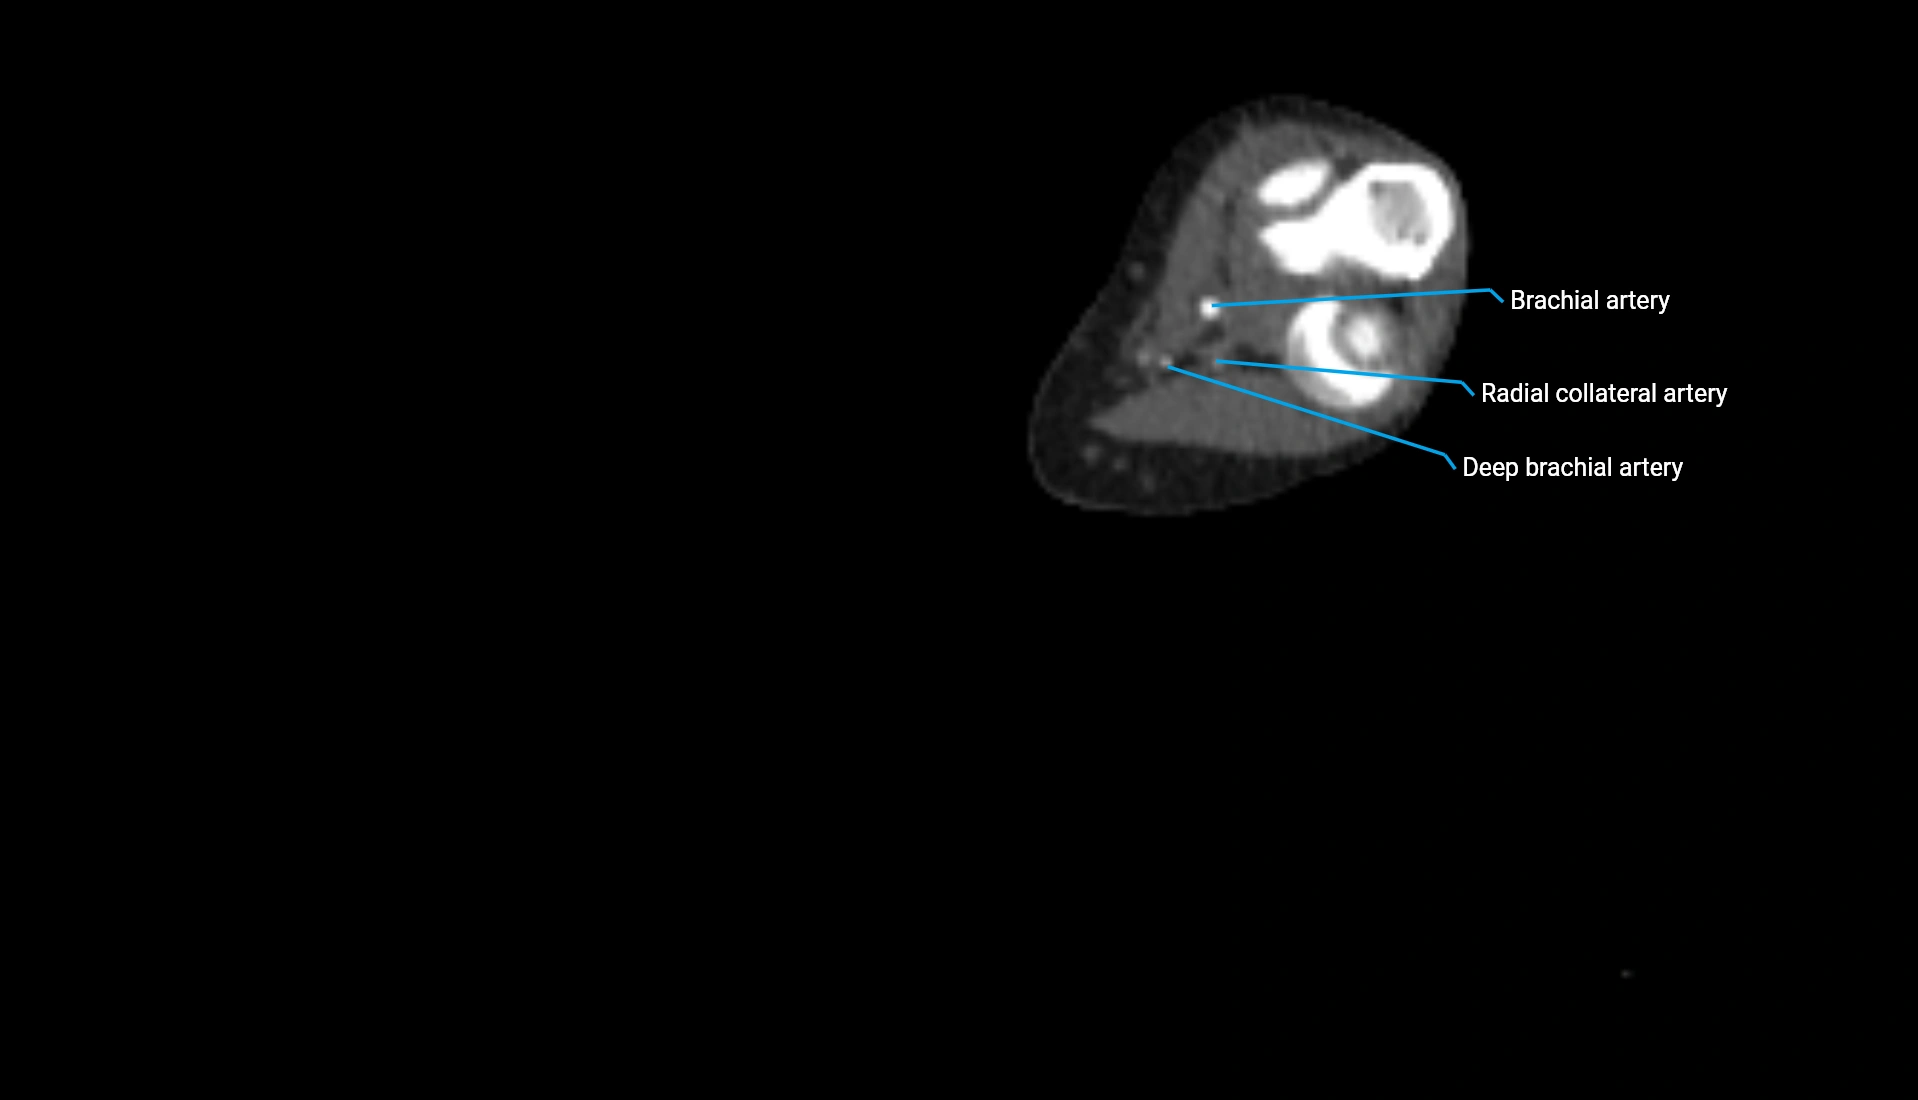

CT Appearance

Non-Contrast CT:

• Cortex: High-density, sharply defined

• Subchondral bone: Dense cancellous matrix

• Articular surface: Smooth concave contour articulating with the capitellum

• Excellent for evaluating bone integrity, alignment, and subtle fractures